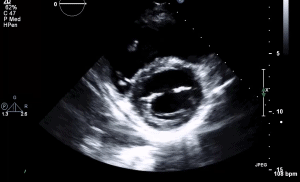

5 RVF PSAX AV